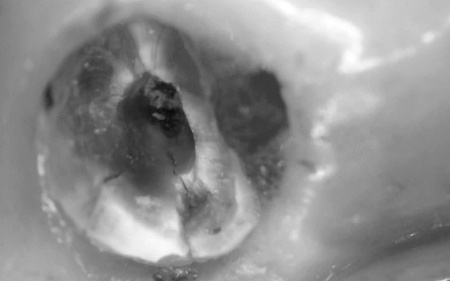

| 行ったご提案 ・治療内容 | 痛みが出ているブリッジ周辺の治療として、ブリッジの土台となっていて、歯根が割れている手前の歯(第2小臼歯)は抜き、根尖病巣を発症している奥の歯(第2大臼歯)は、根管治療を行います。 根管治療とは、感染した神経を取り除いて、歯根内部を清掃・消毒する治療方法のことです。 抜歯と根管治療を行ったあとは、欠損部を補うために、2本のインプラントを埋入する方法を提案しました。 インプラントを埋入するために必要な骨量が足りない場合は、鼻の空洞(上顎洞)の粘膜を少しずつ押し上げて骨を増やす「ソケットリフト」を併用することもお伝えしています。 インプラント治療のメリット インプラント治療のデメリット それぞれの方法について丁寧にお伝えした結果、治療に同意いただきました。 まずは、右上手前の歯(第2小臼歯)を抜きました。 抜歯後は、インプラント治療を行うために、歯を支える骨(歯槽骨)の回復を待つ必要があり、最低でも6ヶ月を要します。 約2ヶ月後、インプラントと骨が結合したことを確認して、右上奥歯2本の仮歯を作製し、手前の歯槽骨が再生するまで経過観察を継続します。 約4ヶ月後、歯槽骨の再生が確認できたため、もう1本のインプラントを埋入しました。 当院のインプラント治療は、施術の安全性と長期的な使用を可能にすることを優先して治療を行うため、通常は抜歯後に歯槽骨の治癒を待ってからインプラントの埋入を行っています。 右上奥歯2本に仮歯が入り、噛み合わせが安定した状態になったため、根尖病巣を発症している右上奥歯の治療を開始します。 また、インプラントに装着する人工歯を作製する前に、歯科医院で歯を白くするオフィスホワイトニング治療を希望されたため、治療期間がやや長くなっています。 最後に、完成した人工歯を装着し、見た目や噛み合わせに問題がないことを確認して、治療を終了しています。 |

治療中